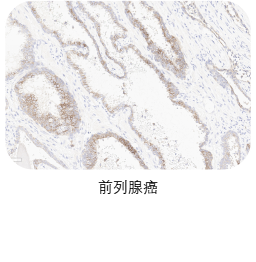

★ 验证充分:三阴性乳腺癌、前列腺癌、胰腺癌、卵巢癌、皮肤癌临床样本充分验证

❷ 适应症癌种染色

选取肿瘤组织样本用于敏感性染色,TROP2一抗染色阳性细胞细胞质和/或细胞膜特异性阳性着色(染色强度≥1),无非特异性着色(染色强度<1),无背景染色(染色强度<1 )。

ACRO IHC实验室目前已建立了成熟的TROP2染色方法与判读体系,适用三阴性乳腺癌、前列腺癌、胰腺癌、卵巢癌、皮肤癌等多个癌种,可快速用于相关肿瘤的临床试验入组筛选与样本检测,部分结果展示如图所示。